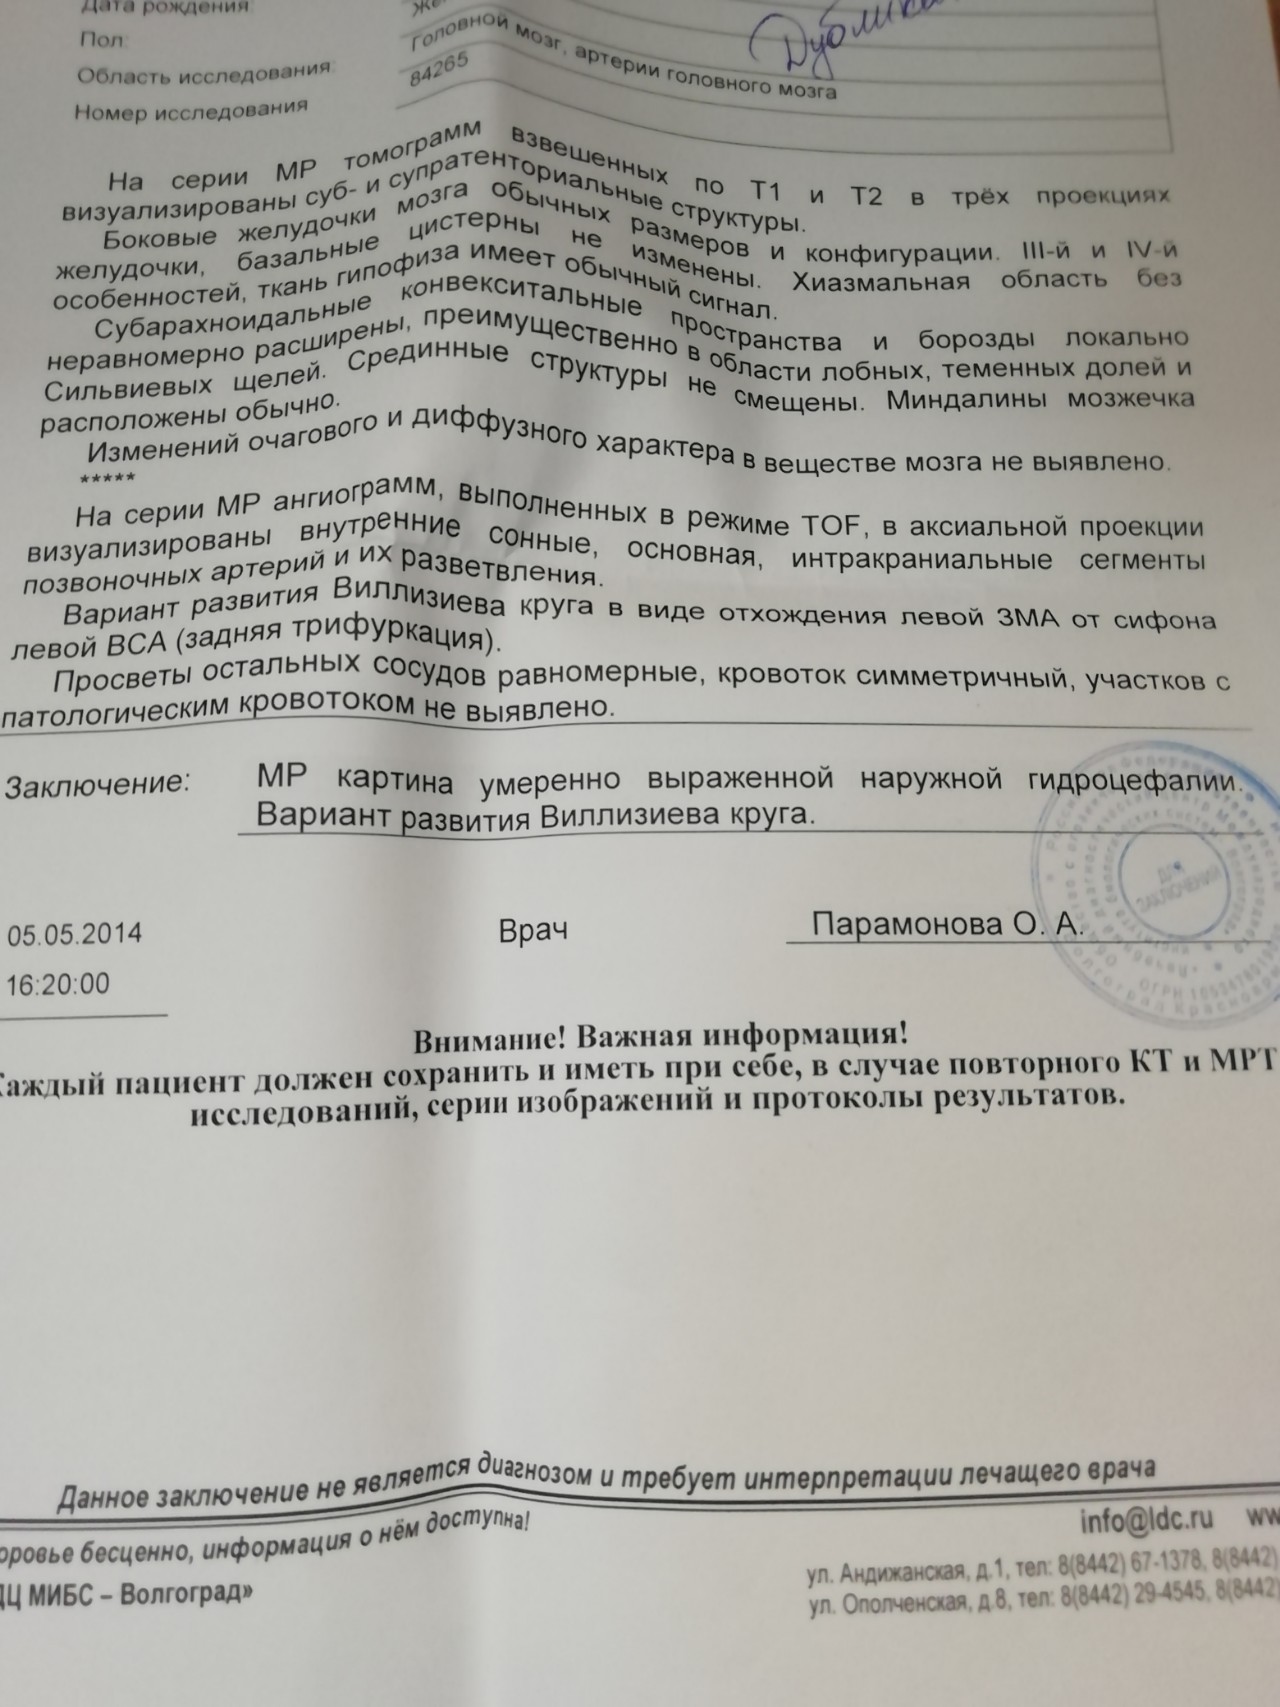

МРТ головного мозга: Расшифровка снимков и Интерпретация

Раздел: Визуальные уроки